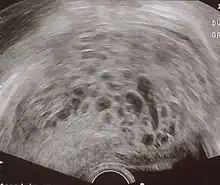

Transvaginal ultrasonography showing a molar pregnancy. -

Molar pregnancy in ultrasound -